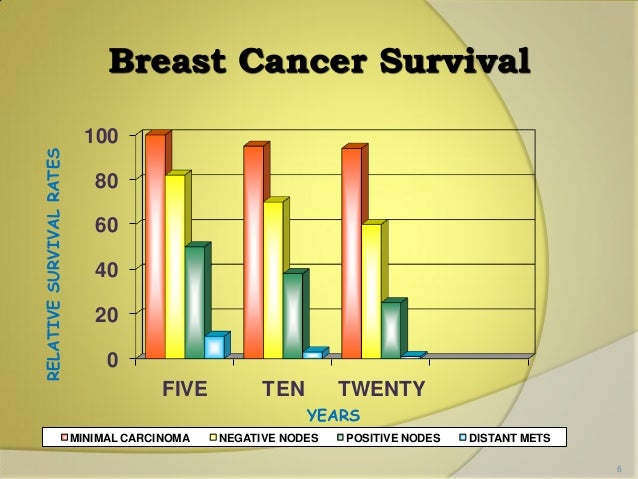

Data That Shows Early Detection Rather Than Late Detection In Breast Cancer